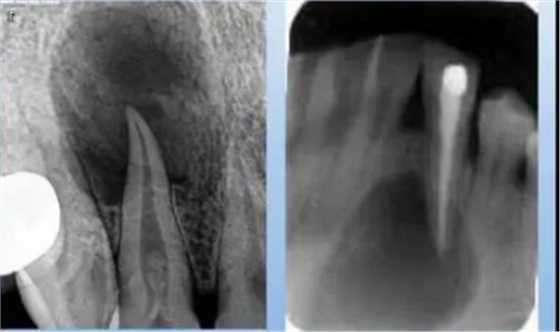

3.根尖囊肿

病理及临床:囊肿内棕黄色液体,常含胆固醇结晶。早期无症状,囊肿长大使骨皮质变薄,可扪及乒乓感,明显增大可致骨质完全吸收,扪及波动感。

X线表现:可见病原牙,透射区边界清晰锐利,边缘有致密的骨硬板。

(1) 致密性骨炎

临床表现:好发于年青人,常见下颌第一磨牙,常有大龋坏,无症状。

X线表现:骨小粱增粗、变密,骨髓腔变窄、消失;

硬化区与正常组织无明显分界;

牙周膜间隙增宽,根尖无增粗。

(2) 牙骨质增生

临床表现:多无症状,发现于拔牙困难或X片

X线表现:牙根粗大;牙周膜间隙变窄或消失。